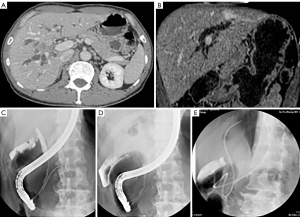

The ERCP procedure

All ERCP procedures were carried out by 6 experienced endoscopists who had cumulatively performed more than 1,000 ERCPs in the past. Preprocedure, computed tomography, and magnetic resonance cholangiopancreatography (MRCP) specifics were obtained for all the included patients and were used to confirm the diagnosis and grade of hilar block. This information was also used to preselect the intended lobe or segment for drainage (based on the liver volume being drained and ductal dilatation). Prophylactic intravenous antibiotics (third generation cephalosporins) were initiated 1 hour before the procedure and continued for 3 days. The ERCP was performed using the standard procedure noted in our previous paper (10). After bile duct cannulation had been successfully performed, a hydrophilic guidewire (Radifocus Guide Wire M, RF-GA35263M, TERUMO, Japan) was advanced through the malignant stenosis into the preselected intrahepatic dilated duct based on MRCP under fluoroscopic guidance. A papillotome was then passed over the guidewire across the stenosis until bile was aspirated (minimum 5–10 mL) to confirm the position and to decrease the intraductal pressure. ACC was then performed by injecting 10 to 15 mL of air, and the opacified ductal system was compared with the segment intended for drainage using MRCP images. If the guidewire failed to pass through the structure into the dilated duct, iodine contrast was injected to obtain a roadmap (these patients were then enrolled into the ICC group). A cytology brush (Cytomax II, Cook Medical LLC, Bloomington, IN, USA) was then used for cytopathologic examination. After the targeted bile duct was cannulated, an endoscopic nasobiliary drainage (ENBD) tube (with or without plastic stent) was placed in the bile duct. The stents used were 7- and 8.5-Fr biliary plastic stents, and the drainage tube was a 7-Fr ENBD tube. In our institution, we prefer a unilateral ENBD to the future lobe as an initial preoperative drainage procedure with hilar cholangiocarcinoma (Figure 1), a method that is accepted in Japan (7,11). For palliative treatment, a plastic stent (with or without ENBD) was implanted in the dilated bile duct (Figure 2).